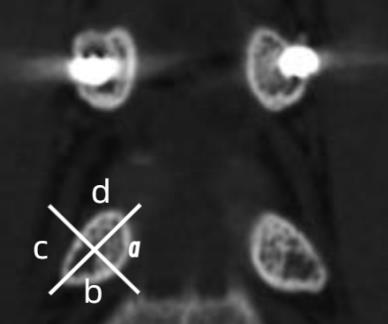

Objective To analyze the correlation between the poor position of pedicle screw after lumbar internal fixation and the occurrence of postoperative neurological symptoms. Methods The clinical data of patients who underwent lumbar pedicle screw surgery in our hospital from January 2017 to December 2023 were analyzed retrospectively. Record the patient's sex, age, diagnosis, surgical segment, the presence of postoperative neurological complications, the types of neurological complications. According to the postoperative CT, the screw penetration zone and grade were evaluated, and the distribution of different pedicle screw penetration types was recorded. The correlation between different types of pedicle screw penetration and postoperative neurological symptoms was analyzed. Results A total of 184 patients were included, including 80 males and 104 females. Age ranged from 18 to 82 years, with an average of 60.1 ± 14.2 years. 35 patients developed new neurological symptoms after operation. The incidence of postoperative neurological symptoms caused by pedicle medial quadrant screw penetration and lower quadrant screw penetration was higher than that of pedicle superior quadrant and lateral quadrant screw penetration. From L1 to L5, the risk of postoperative neurological symptoms caused by screw penetration in the medial quadrant of the pedicle increases gradually. When the penetration distance of pedicle medial quadrant screws in L4 and L5 segments is ≥ 2mm, the risk of postoperative neurological symptoms is high. When the penetration distance of pedicle medial quadrant screws in L1, L2 and L3 segments is greater than 4mm, the risk of postoperative neurological symptoms is high. The distance of pedicle screw penetrating the medial quadrant of pedicle was positively correlated with the incidence of postoperative neurological symptoms (P < 0.05). Conclusion The lateral and superior quadrants of the pedicle may be regarded as safety zones for lumbar pedicle screw placement. For the L1 ~ L3 segments, screw penetration depth should not exceed 4 mm; whereas for the L4 ~ L5 segments, the safety threshold must be strictly controlled within 2 mm.